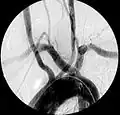

Aberrant right subclavian artery at angiography.